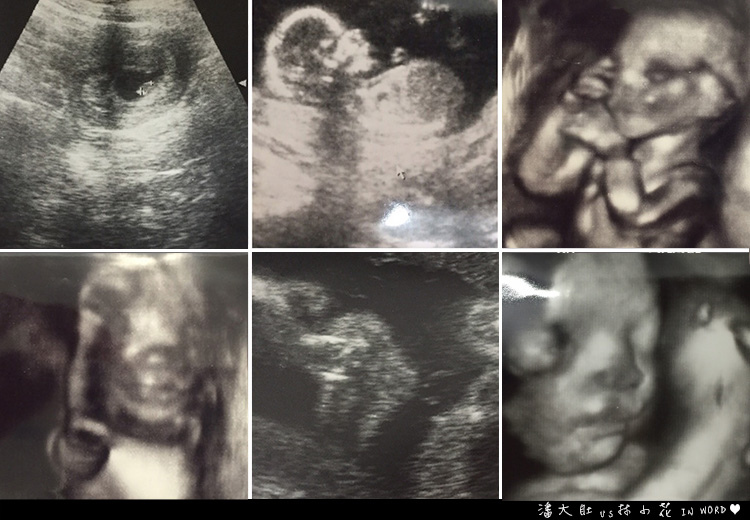

我看著診所不是很先進的螢幕

光是看這一點點,怎麼就可以知道有寶寶了呢~我可是怎麼看都看不懂呢...

但是在照超音波的過程中

林醫生笑容滿面的安撫我

告訴我「寶寶嘴巴好可愛,沒有兔唇喔!」

「鼻子高高的不要擔心唐氏症的問題,通常唐氏症的話鼻子就不會這麼高了」

「妳看,也沒有無腦、水腦的問題,妳下次來,我幫妳數她的手指頭喔!」

我瞬間,覺得整顆心都放下了!

小寶貝,妳的鼻子真的高高的耶!

光是照完超音波後就對我說:「妳胎位很低喔!」

今天照超音波的時候

寶貝把手擋在臉上,好可愛!

潘大肚一直說「我家寶貝是瓜子臉耶!像爸爸!」(好想飛踢他)

寶貝又把手擋在臉上了~(媽媽想看妳嘛)

林醫師說,一定是妳和潘大肚其中有一個人睡姿就是這個樣子

我轉過頭看了一下潘大肚,他不斷在竊笑....

我就說:「對啊.....跟爸爸的睡姿一模一樣.....」